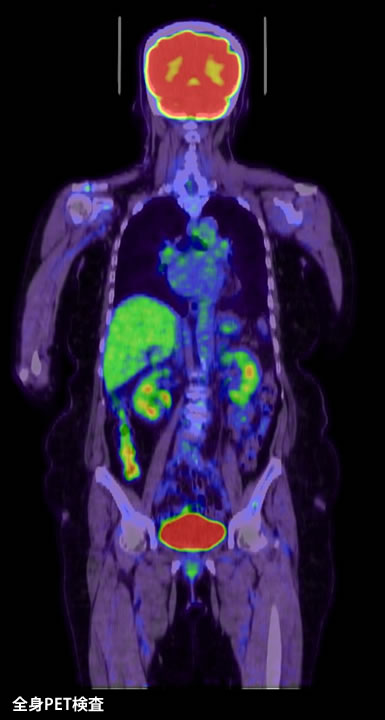

中枢神経原発悪性リンパ腫はCTやMRIなどの画像検査で脳内病変の評価を行います。病変は脳深部に存在することが多く、またしばしば複数の病変として認められることもあります。中でもMRIの特殊撮影(拡散強調画像)やブドウ糖代謝を利用したポジトロンCT(PET)検査は特異度が高いため、当院ではこれらの検査を行って他の脳腫瘍との鑑別を行っています。またPET検査は全身撮影を行い、体幹部のCT検査などと併せて腫瘍の全身への広がりを判定します。そのほかに髄液を採取して細胞診を行うなどして、総合的に診断を進めていきます。そして最終的には手術で病理診断を確定します。